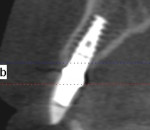

Following the technique for immediate extraction, immediate implant placement and provisionalization procedures outlined previously, the patient had teeth Nos. 7 through 9 removed by atraumatic, minimally invasive means, debridement was accomplished, and 3 implants were placed: a NobelActive implant (Nobel Biocare, nobelbiocare.com) measuring 3.5 mm x 11.5 mm at No. 7; and 2 NobelActive implants measuring 3.5 mm x 13.5 mm placed at Nos. 8 and 9 respectively, with each implant obtaining an ISQ of 50 Ncm at placement. Implant placement was accomplished by a minimally invasive (flapless) protocol. Reconstruction of the missing buccal plate in the region of teeth Nos. 7 through 9 was accomplished once again by an allogenic, mineralized, cancellous 1-mm to 2-mm-particle-size bone graft (LifeNet Health, lifenethealth.org) condensed into the peri-implant defects, to the level of the crest of the bone-level NobelActive implant (Figure 16). Provisional QuickTemp Abutment Conical Connection (Nobel Biocare) were screwed into place, and an immediate provisional restoration constructed from the retrofitted TempStent II surgical guide32 provisionalization system. The provisional restoration was cemented with Temp-Bond™ Clear (Kerr, kerrdental.com), and the excess cement was removed. The patient was allowed to follow a 3-month healing and observation period after which fixture-level impressions were obtained and computer-aided design and computer-aided manufacturing custom-milled zirconia abutments were constructed. This was followed by a second set of provisional restorations the patient utilized for an additional 2 months. Final impressions were taken of the zirconia abutments, and final all-ceramic restorations were constructed and cemented into place. The case’s complete clinical view can be seen in Figure 17. Figure 18 shows the 4.5-year post-treatment clinical view, while Figure 19 shows the 4.5-year post treatment computed tomography (CT) scan serial view. Please note that the total reconstruction of the buccal bone structures achieved by the minimally invasive bone graft procedure was accomplished following the technique previously outlined.

A 49-year-old nonsmoking male presented for treatment of his advanced tooth loss, terminal dentition, residual infection after dental treatment, and recurrent sinus infections. His dental history consisted of multiple attempts at conventional treatment approaches to prolong tooth longevity, several implant procedures to replace failing endodontically treated teeth and edentulous sites (all resulting in repeated failure of treatment), compromised esthetics, and various secondary infectious diseases related to previous failures of dental treatment. The pretreatment CT scan view of the maxillae and several serial views (Figure 20) demonstrated multiple edentulous sites, residual sinus infections, failing implant procedures with large alveolar defects, and the remaining dentition, which can be classified as a “terminal dentition.” After reviewing multiple treatment options with the patient ranging from conventional fixed and removable options, to partial implant reconstruction with extensive bone replacement procedures recommended, the patient opted for removal of most of the remaining dentition, correction of sinus pathology, multiple implant placement, and immediate provisionalization procedures, most accomplished by a conservative, minimally invasive protocol (except for the sinus regions, which required flap access and a lateral-wall osteotomy), and immediate loading of the implants at the initial and only surgical procedure planned. After extensive medical and dental histories were taken, medical clearance for the preexisting sinus infections was obtained, and a complete dental workup consisting of a facebow transfer, mounted maxillary and mandibular pretreatment models, a complete diagnostic waxup of both the hard and soft tissues required to be replaced, and construction of the TempStent II surgical guide and provisionalization system, the patient was given an appointment for the complex surgical visit. During this surgery, remaining dentition and implants were removed, ten implants in the maxillary arch were inserted, and bilateral sinus elevations and alveolar reconstruction was performed along with peri-implant bone grafting and immediate provisionalization. In the mandibular arch, removal of the remaining dentition was done, except for teeth Nos. 21, 22, 27, and 28, and six implants were placed and immediately provisionalized, keeping the patient in the planned first-molar occlusion scheme. The immediate post-treatment panoramic view can be seen in Figure 21. After an uneventful healing for 4.5 months, the patient then initiated the final reconstructive phase of his treatment. A 7-year post-treatment clinical view can be seen in Figure 22, with the 7-year post-treatment CT panoramic scan, axial and serial views of the maxillary central incisor seen in Figure 23.